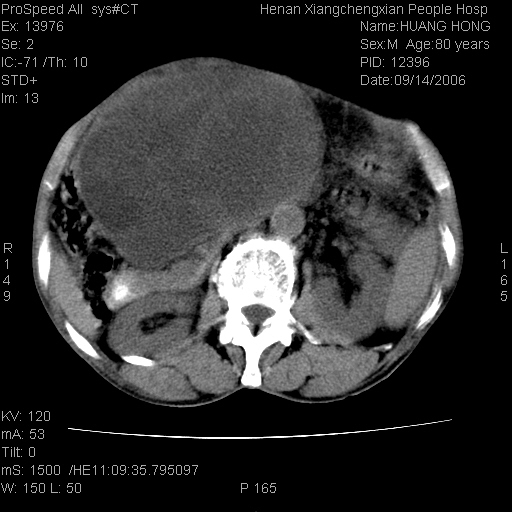

患者, 男, 80岁, 发现上腹部包块1年余,无其它不适.2006-9-14ct片是喝水后扫描2006-9-15ct片没喝水扫描![]() ![]() ![]() ![]() ![]() ![]() ![]() ![]() ![]() ![]() ![]() ![]() ![]() ![]() ![]() ![]() 以上是喝水片 以下是空腹片 ![]() ![]() ![]() ![]() ![]() ![]() ![]() ![]() ![]() ![]() ![]() ![]() ct:胰腺前方、肝脏与胃之间可见巨大类圆形囊性低密度影,大小约152mmx145mmx118mm,上缘平t11椎体上缘,下缘平l3椎体下缘,密度均匀,ct值15hu,其内呈多房分隔,囊壁薄且光滑,边界清晰,周围组织及器官明显受压。肝脏实质内未见异常密度影,胆囊未见异常,胰腺密度未见异常,脾脏大小、形态及密度未见异常,腹膜后间隙未见肿大淋巴结影。 印象:胰腺前方、肝脏与胃之间巨大类圆形囊性低密度影.性质待定。多考虑:.肠系膜巨大囊肿。 守望可可西里发言:支持楼主,考虑肠系膜囊肿,多为小肠系膜。 ysxyy发言:我总觉得这个病人虽然很像肠系膜囊肿,但还是应该强化一下; 下面这几幅图里肿块和主动脉的关系不太清,不知能否除外血管性来源? ![]() ![]() ![]() 病理结果:横结肠系膜间叶瘤.部分区域间质细胞增生活跃. 病理图片 ![]() 良性间叶瘤:是指由两种或两种以上的间叶组织所构成的混合性肿瘤.肿瘤仅发生在腹膜后和肠系膜,.前者较后者多发.良性间叶瘤常发生在肾或四肢,腹膜后较少见,各年龄均可发病.女多与男,预后较好,但术后易复法. 恶性间叶瘤:由两种以上恶性间叶组织成分组成. 光镜:肿瘤由脂肪/血管/平滑肌构成. 原贴地址: http://www.radinet.com.cn/forum_view.asp?forum_id=4&view_id=16217 ok |